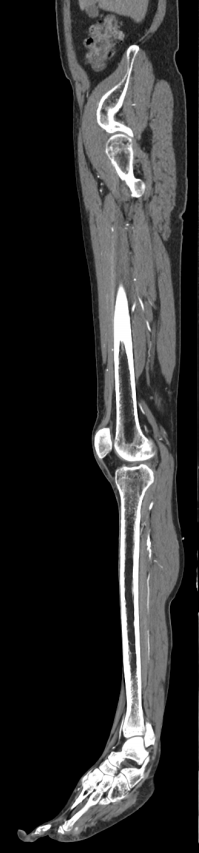

Мультиспиральная компьютерная томография является современным методом обследования сосудистой системы нижних конечностей. Такое исследование по-другому называется КТ-ангиография. Методика позволяет с помощью рентгеновского излучения получить посрезовые снимки и после цифровой обработки создать объемные модели кровеносной системы обеих ног.

В наших медицинских центрах КТ-ангиография нижних конечностей выполняется на современных мультиспиральных компьютерных томографах экспертного уровня TOSHIBA AQUILION. Аппараты послойно сканируют область исследования, одномоментно выполняя множество тончайших срезов. В результате получаются снимки высокого качества и трехмерные модели с изображением даже мелкой сосудистой сети нижних конечностей. При этом методика скоростного мультисрезового сканирования обеспечивает минимальную дозу рентгеновского облучения для пациента.

• КТ сосудов от бифуркации аорты до стопы (данный протокол обследования включает в себя полное обследование сосудов нижних конечностей, включая стопы)